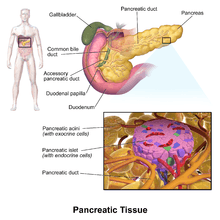

The pancreatic islets or islets of Langerhans are the regions of the pancreas that contain its endocrine (i.e., hormone-producing) cells, discovered in 1869 by German pathological anatomist Paul Langerhans.[2] New studies show that the pancreatic islets constitute approximately 4.5% of the pancreas volume[1] and receive 10-15% of its blood flow.[3] The islets of Langerhans are arranged in density routes throughout the healthy human pancreas.[1]

Structure

There are about 3 million islets distributed in the form of density routes throughout the pancreas of a healthy adult human,[1] each of which measures an average of about 0.1 mm (109 µm) in diameter.[1][4]:914 Each is separated from the surrounding pancreatic tissue by a thin fibrous connective tissue capsule which is continuous with the fibrous connective tissue that is interwoven throughout the rest of the pancreas.[4]:914 The combined mass of the islets is 2 grams.[1] Islets of Langerhans can also form super structures called Islet clusters which are composed of small islets that surround large blood vessels.[1] The roundness of islets along the pancreas has also been quantified through the Index of Sphericity method.[1] Thus, the islets closest to the spherical form are mainly found in the pancreas tail whereas the islets farthest from the spherical form are found in the pancreas neck.[1]

Histology

Hormones produced in the pancreatic islets are secreted directly into the blood flow by (at least) five types of cells. In rat islets, endocrine cell subsets are distributed as follows:[5]